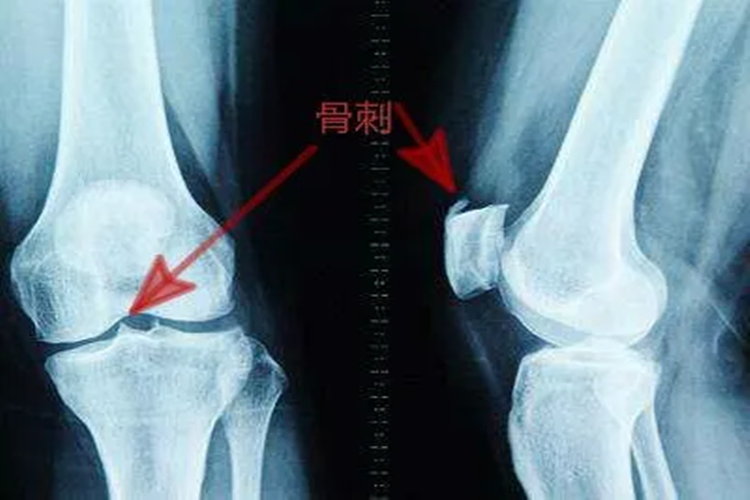

髌骨位于膝关节前,出现骨质增生时,可能引起局部组织明显异常,同时进行影像学检查时,可以看到局部密度增高、变形等。

影像学特征:局部会出现骨质密度增高,骨小梁增粗、增多、密集,骨皮质增厚,骨髓腔变窄或消失,伴有或不伴有骨骼的增大变形。